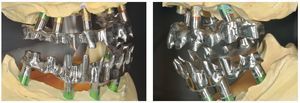

Una vez aprobada la planificación, mediante el software CAD se transmiten los datos en formato STL (Standard Transformation Language o Stereolithography Language) a otro software CAM, el cual procesa nuevamente los datos suministrados para enviarlos en «idioma de máquina» a la fresadora (Zfx, ULTRASONIC 20, Denttec KG-SAS, Gargazon, Italia) encargada de confeccionar la estructura de titanio (figs. 98 y 99). La utilización de fresadoras industriales de cinco ejes para la confección de este tipo de prótesis garantiza un éxito seguro en cuanto a precisión de ajuste y pasivización, y evita casi todos los riesgos que pueden aparecer durante el colado protésico clásico.

Pese a ello, es importante someter las estructuras a un control visual y mecánico, a fin de corregir eventuales discrepancias menores (figs. 99 a 102). A continuación se procede al montaje utilizando dientes protésicos prefabricados de composite (SR Phonares NHC, Ivoclar Vivadent, Ellwangen, Alemania), los cuales reproducen el tipo funcional correspondiente en virtud de sus propiedades morfológicas y estructurales y se integran armoniosamente en cuanto a su longitud dental (figs. 103 a 105). Durante la comprobación de las restauraciones protésicas, se evalúan clínica y radiológicamente ante todo la pasividad y la precisión del ajuste de la estructura. Acto seguido se lleva a cabo una comprobación de la oclusión y de la dimensión vertical, del estado de las prótesis y del tejido blando en la cresta alveolar, así como la verificación del espacio libre lingual, incluida la fonación, y el apoyo de los labios y las mejillas (figs. 106 y 107). También se debe comprobar la facilidad de higiene de la restauración de acuerdo con las habilidades manuales del paciente. A continuación se debe verificar la posición tridimensional de los dientes anteriores con los labios cerrados y durante la sonrisa, así como el aspecto global de la rehabilitación protésica.

Figs. 99 y 100. Confección de la barra de titanio mediante una fresadora de 5 ejes.

Figs. 101 y 102. Vista lateral de las estructuras atornilladas sobre los modelos.